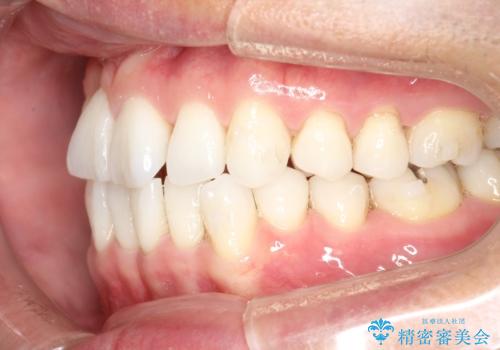

右上の前から2番目の歯が引っ込んで、下の前歯にはガタガタがありました。

上下の歯と歯の間を少量ずつ削りスペースを作り、インビザラインにて並べる計画としました。

目立たずに矯正治療を終えることができたことに満足していただけました。